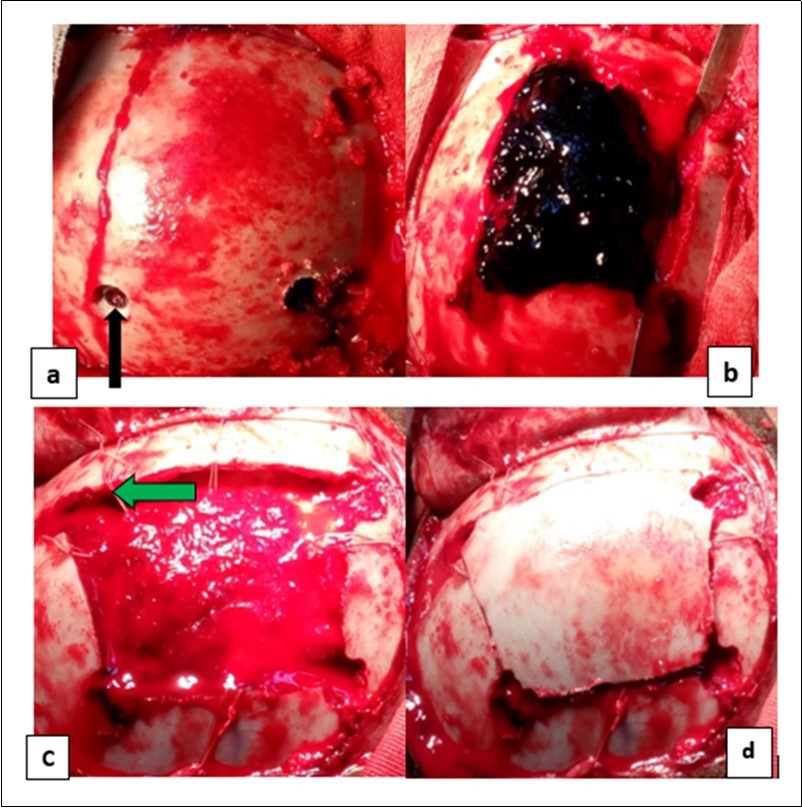

From the point of view of care, two (n=2) (10.52%) children received medical treatment compared to 17 (89.48%) children who received medical-surgical treatment. Neurosurgical treatment consisted of evacuation of the extra dural hematoma. This involved making a skin incision, trepanation (Figure 3 a), a preserved cranial bone flap, evacuation of the extra-dural haematoma (Figure 3 b), haemostasis either of the bone using bone wax or venous or arterial haemostasis by bipolar coagulation as appropriate, suspension of the dura mater (Figure 3 c), replacement of the bone flap (Figure 3 d) and finally suturing of the scalp in two planes. Figure 1, Figure 2, Figure 3.

Figure 3.Operating times for an extra dural hematoma: a) making a cranial bone flap with three drill holes (the black arrows); b) extra dural hematoma after craniotomy (by the blue arrows); c) image showing the dura mater then suspension of the dura mater (the green arrows) and d) image after handing over the bone flap.